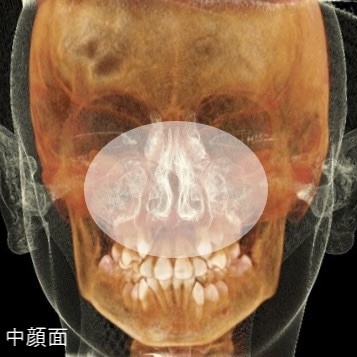

この治療では、歯並びが悪くなる原因の多くを、「中顔面(鼻周りのあたり)の発達不良」に起因する、「顎骨の歪み(上下顎の劣成長)」と捉えています。

中顔面の発達不良

POINT

ポイントがここです。

顎が小さいことの原因、口呼吸によって、舌が上顎から離れます。舌の支えがなくなった中顔面(上顎)は、重力の影響から下方へと成長方向を変えます。中顔面の正しい成長方向とは、「上前方」。上顎についた舌は本来、そのガイド役です。

RAMPAでは、歯並びが悪くなる原因の多くを、中顔面の発達不良と考えています。

本来、中顔面は上前方への成長が健全な成長方向です。しかし現在、それが下方成長として現れている症例が非常に多く見られます。これがまず、「中顔面の発達不良」です。これにより、顎骨に歪みが生じることで、様々な不正咬合として表出します。